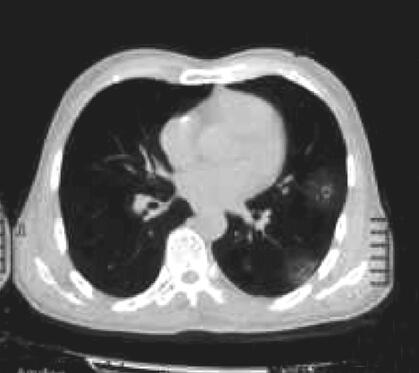

图2 2014年11月21日双肺囊样空腔病灶增多,双侧气胸,右侧胸腔气体量较前增多